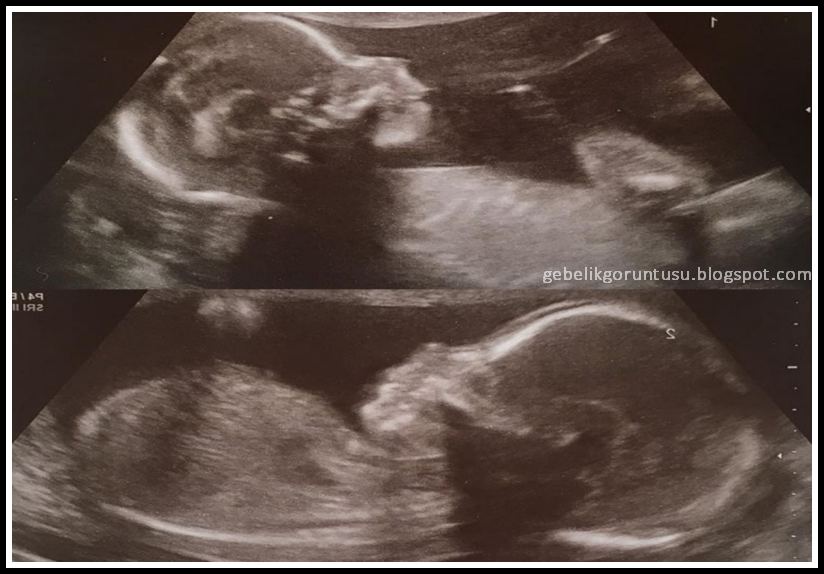

20 haftalık gebelik ultrason görüntüsü (görüntüleri):

| 20 haftalık gebelik ultrason görüntüsü |